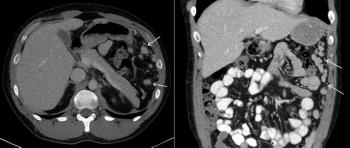

A 25-year-old man with abdominal discomfort undergoes CT imaging to determine its cause. What is your diagnosis?